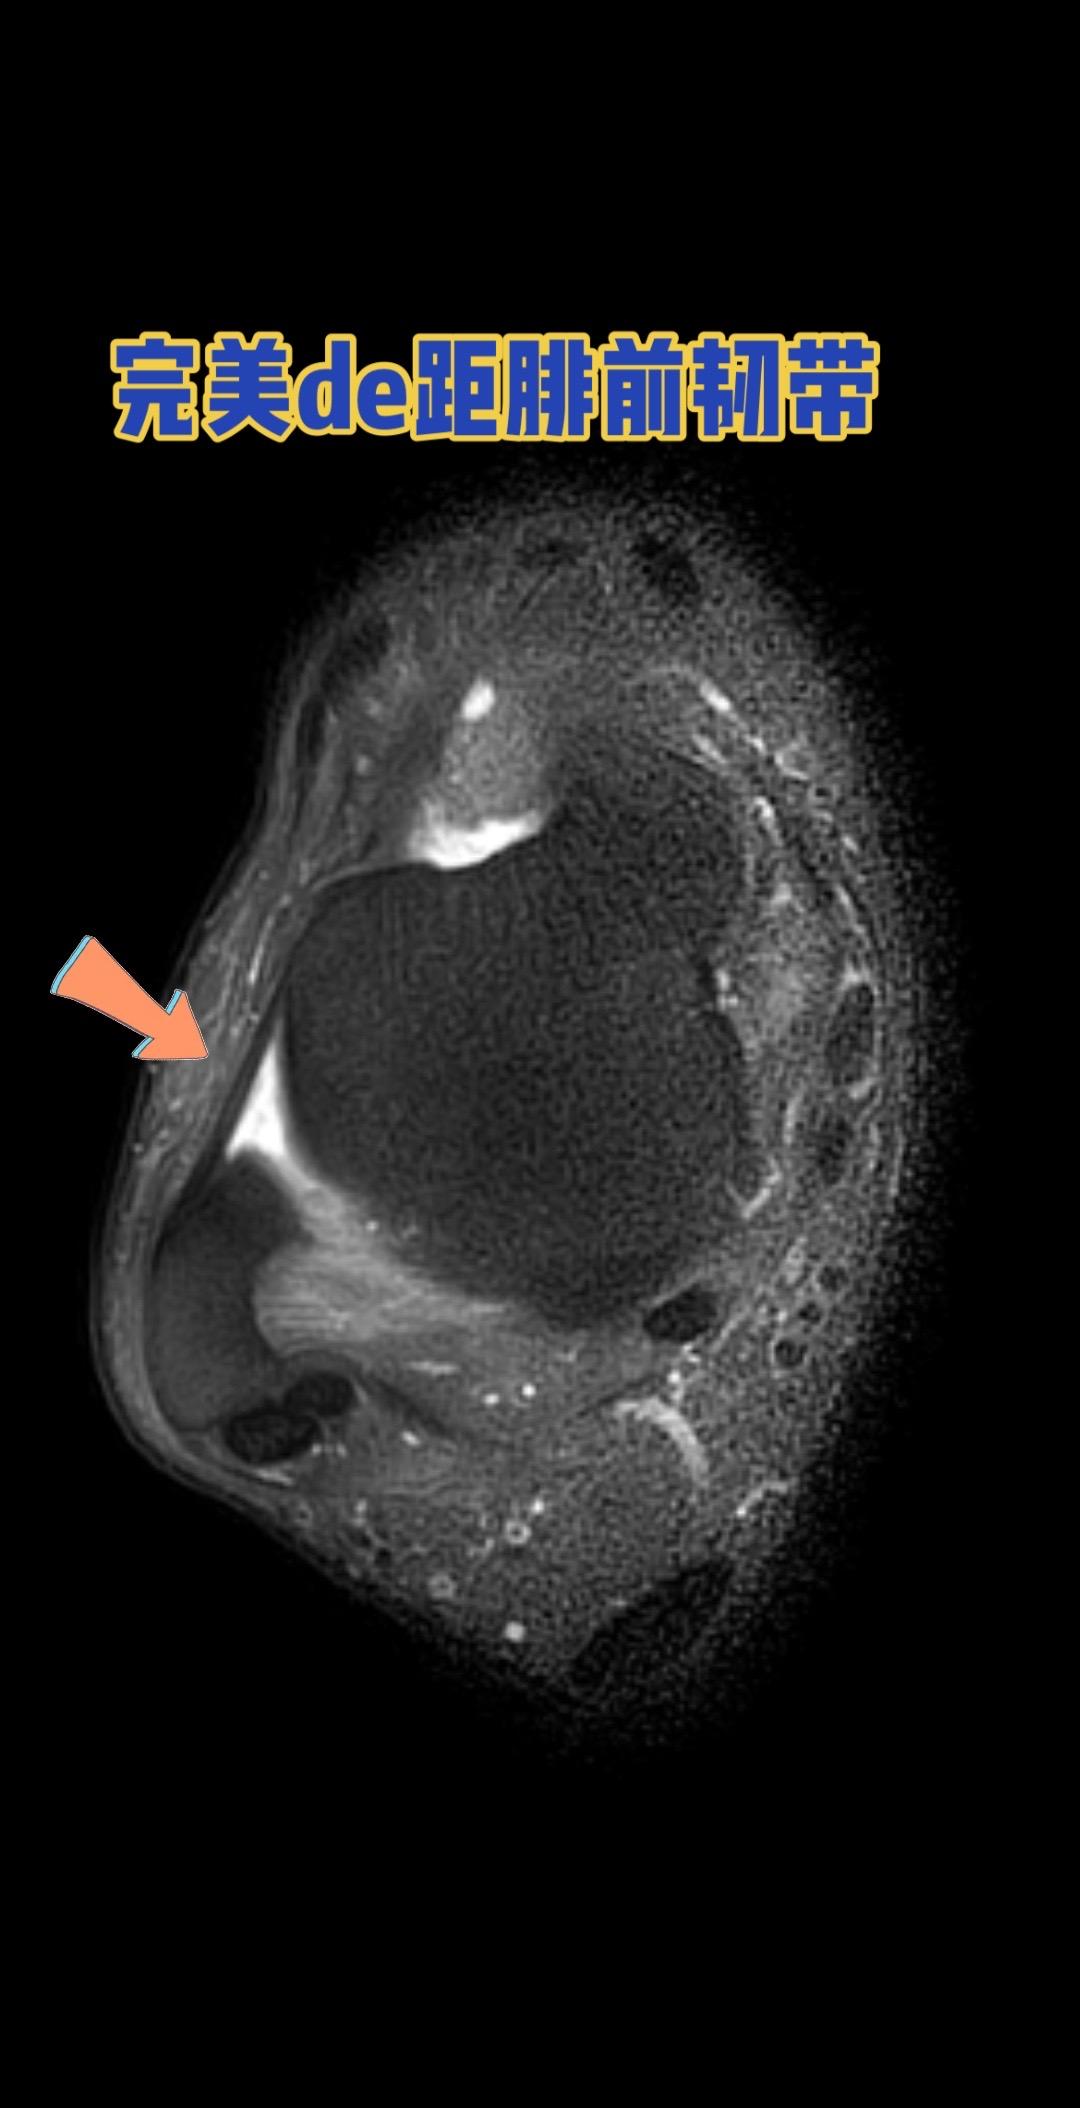

距腓前韧带。👉 健康的距腓前韧带长这样! 距腓前韧带